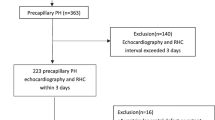

We herein performed a retrospective longitudinal observational cohort study. 153 patients with precapillary pulmonary hypertension according to RHC evaluation (mPAP ≥ 25 mmHg, PCWP ≤ 15 mmHg) were evaluated. We included subjects with WHO group I and IV PH. According to the availability of data for all time points, 130 patients, aged 18 to 90 years, were included in the study. Clinical performance status, laboratory tests, echocardiography, capillary blood gas analysis, and pulmonary function testing at five different time points (baseline assessment and yearly follow-ups from 2015 to 2018) were analysed. The study inclusion process is depicted in Additional file 1: Fig S1.

Additional file 1: Fig. S1.

STROBE diagram for analysis cohort. Fig. S2. Model selection, score calculation, and score testing scheme for FPHR risk model refinement. Fig. S3. Kaplan–Meier analysis for candidate FPHR3p-modifying variables. Table S1. Variables used for risk stratification according to five different risk assessment tools. Table S2. Cut-offs used to define risk category for each risk parameters. Table S3. Baseline hemodynamic characteristics assessed by right-heart catheter at rest. Table S4. Mortality risk models including right-heart catheter parameters at baseline. Table S5. Mortality risk-assessment models according to the three-parametric FPHR and the mRASP model.